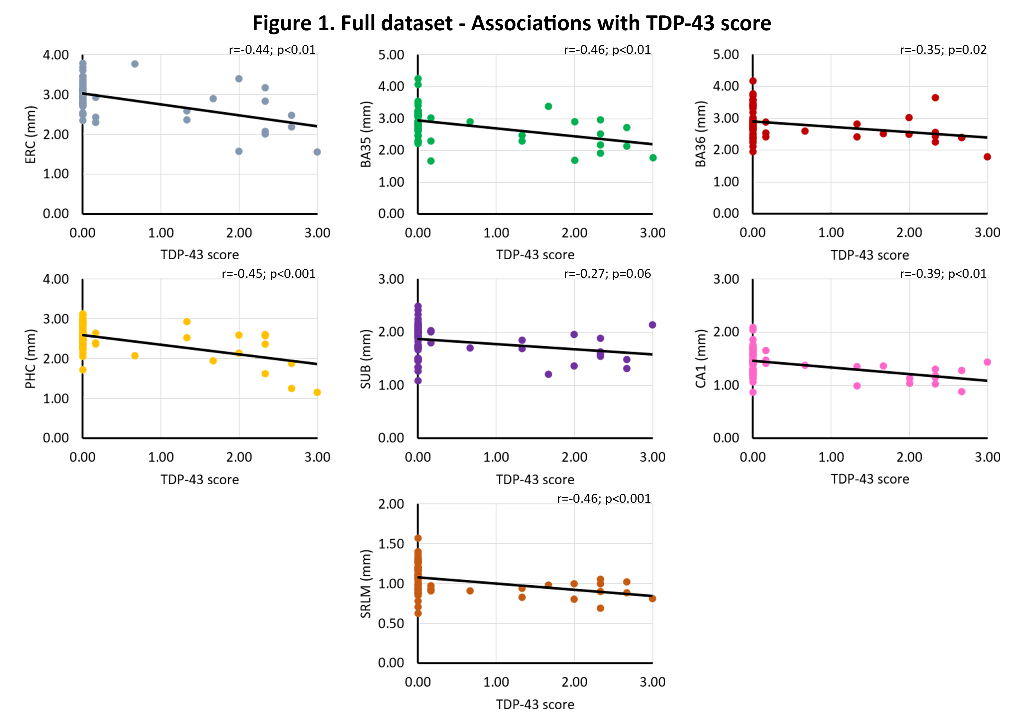

Tau, TDP-43, β-amyloid and α-synuclein pathology were rated (0-absent – 3-frequent) in the hippocampus and entorhinal cortex (ERC) of 58 individuals with and without neurodegenerative diseases (mean age 74.7 years, 39.7% female). Thickness measurements using a semi-automated approach were obtained from 0.2x0.2x0.2 mm3 post-mortem MRI scans of excised MTL specimens from the contralateral hemisphere in the ERC, Brodmann Area (BA) 35 and 36, parahippocampal cortex (PHC), subiculum (SUB), cornu ammonis (CA)1 and the stratum radiatum lacunosum moleculare (SRLM). Spearman’s rank correlations were performed, correcting for age, sex and hemisphere, including all four proteinopathies in the model.

We find significant associations of 1) TDP-43 with all subregions (r=-0.27 – r=-0.46, trend for subiculum), and 2) tau with ERC (r=-0. 26, trend), BA35 (r=-0.31) and SRLM (r=-0.33). In β-amyloid and TDP-43 negative cases, we find strong significant associations of tau with ERC (r=-0.40, trend), BA35 (r=-0.55), subiculum (r=-0.42), CA1 (r=-0.47) and SRLM (r=-0.38, trend). See figures 1-3.

This unique dataset showed widespread atrophy in relation to TDP-43 pathology and atrophy in early Braak regions and tau pathology. Moreover, the strong association of tau with thickness in early Braak regions in the absence of β-amyloid and TDP-43 is indicative for a role of Primary Age Related Tauopathy in neurodegeneration.